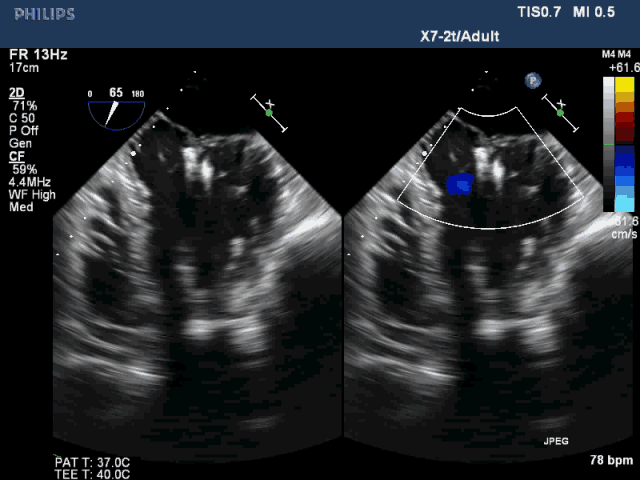

該例患者是一名78歲男性,合并癥較多,基礎(chǔ)心功能差,傳統(tǒng)外科手術(shù)風(fēng)險(xiǎn)極高,故選擇了經(jīng)心尖二尖瓣夾合術(shù)(ValveClamp)。然而,術(shù)前超聲評(píng)估顯示,患者后葉脫垂范圍極大,達(dá)23mm,P2 和P3均有脫垂,反流頸寬度達(dá)13mm。嚴(yán)重二尖瓣反流導(dǎo)致患者心功能很差,血壓較低。如此廣泛的脫垂,使用國(guó)外同類產(chǎn)品完成經(jīng)導(dǎo)管微創(chuàng)二尖瓣修復(fù)也是很有挑戰(zhàn),甚至無(wú)法完成的。葛均波院士團(tuán)隊(duì)分析患者病情后,選擇了使用我國(guó)自主研發(fā)的二尖瓣器械ValveClamp為患者實(shí)施經(jīng)心尖二尖瓣夾合術(shù)。反復(fù)嘗試數(shù)次單個(gè)夾合器夾合后,患者仍有中重度二尖瓣反流。遂采取雙夾合器技術(shù),為患者植入兩個(gè)夾合器,術(shù)后即刻患者反流減少至輕度,二尖瓣跨瓣壓差僅為3mmHg。該例手術(shù)是ValveClamp首例采取雙夾子技術(shù),證明了該器械行雙夾子技術(shù)是安全、可行的。手術(shù)由中山醫(yī)院心內(nèi)科葛均波院士、周達(dá)新教授、潘文志副主任醫(yī)師,心外科魏來教授,心超室的潘翠珍教授、李偉主治醫(yī)師,心外麻的郭克芳教授共同完成。

圖3 植入雙夾合器后反流為輕度